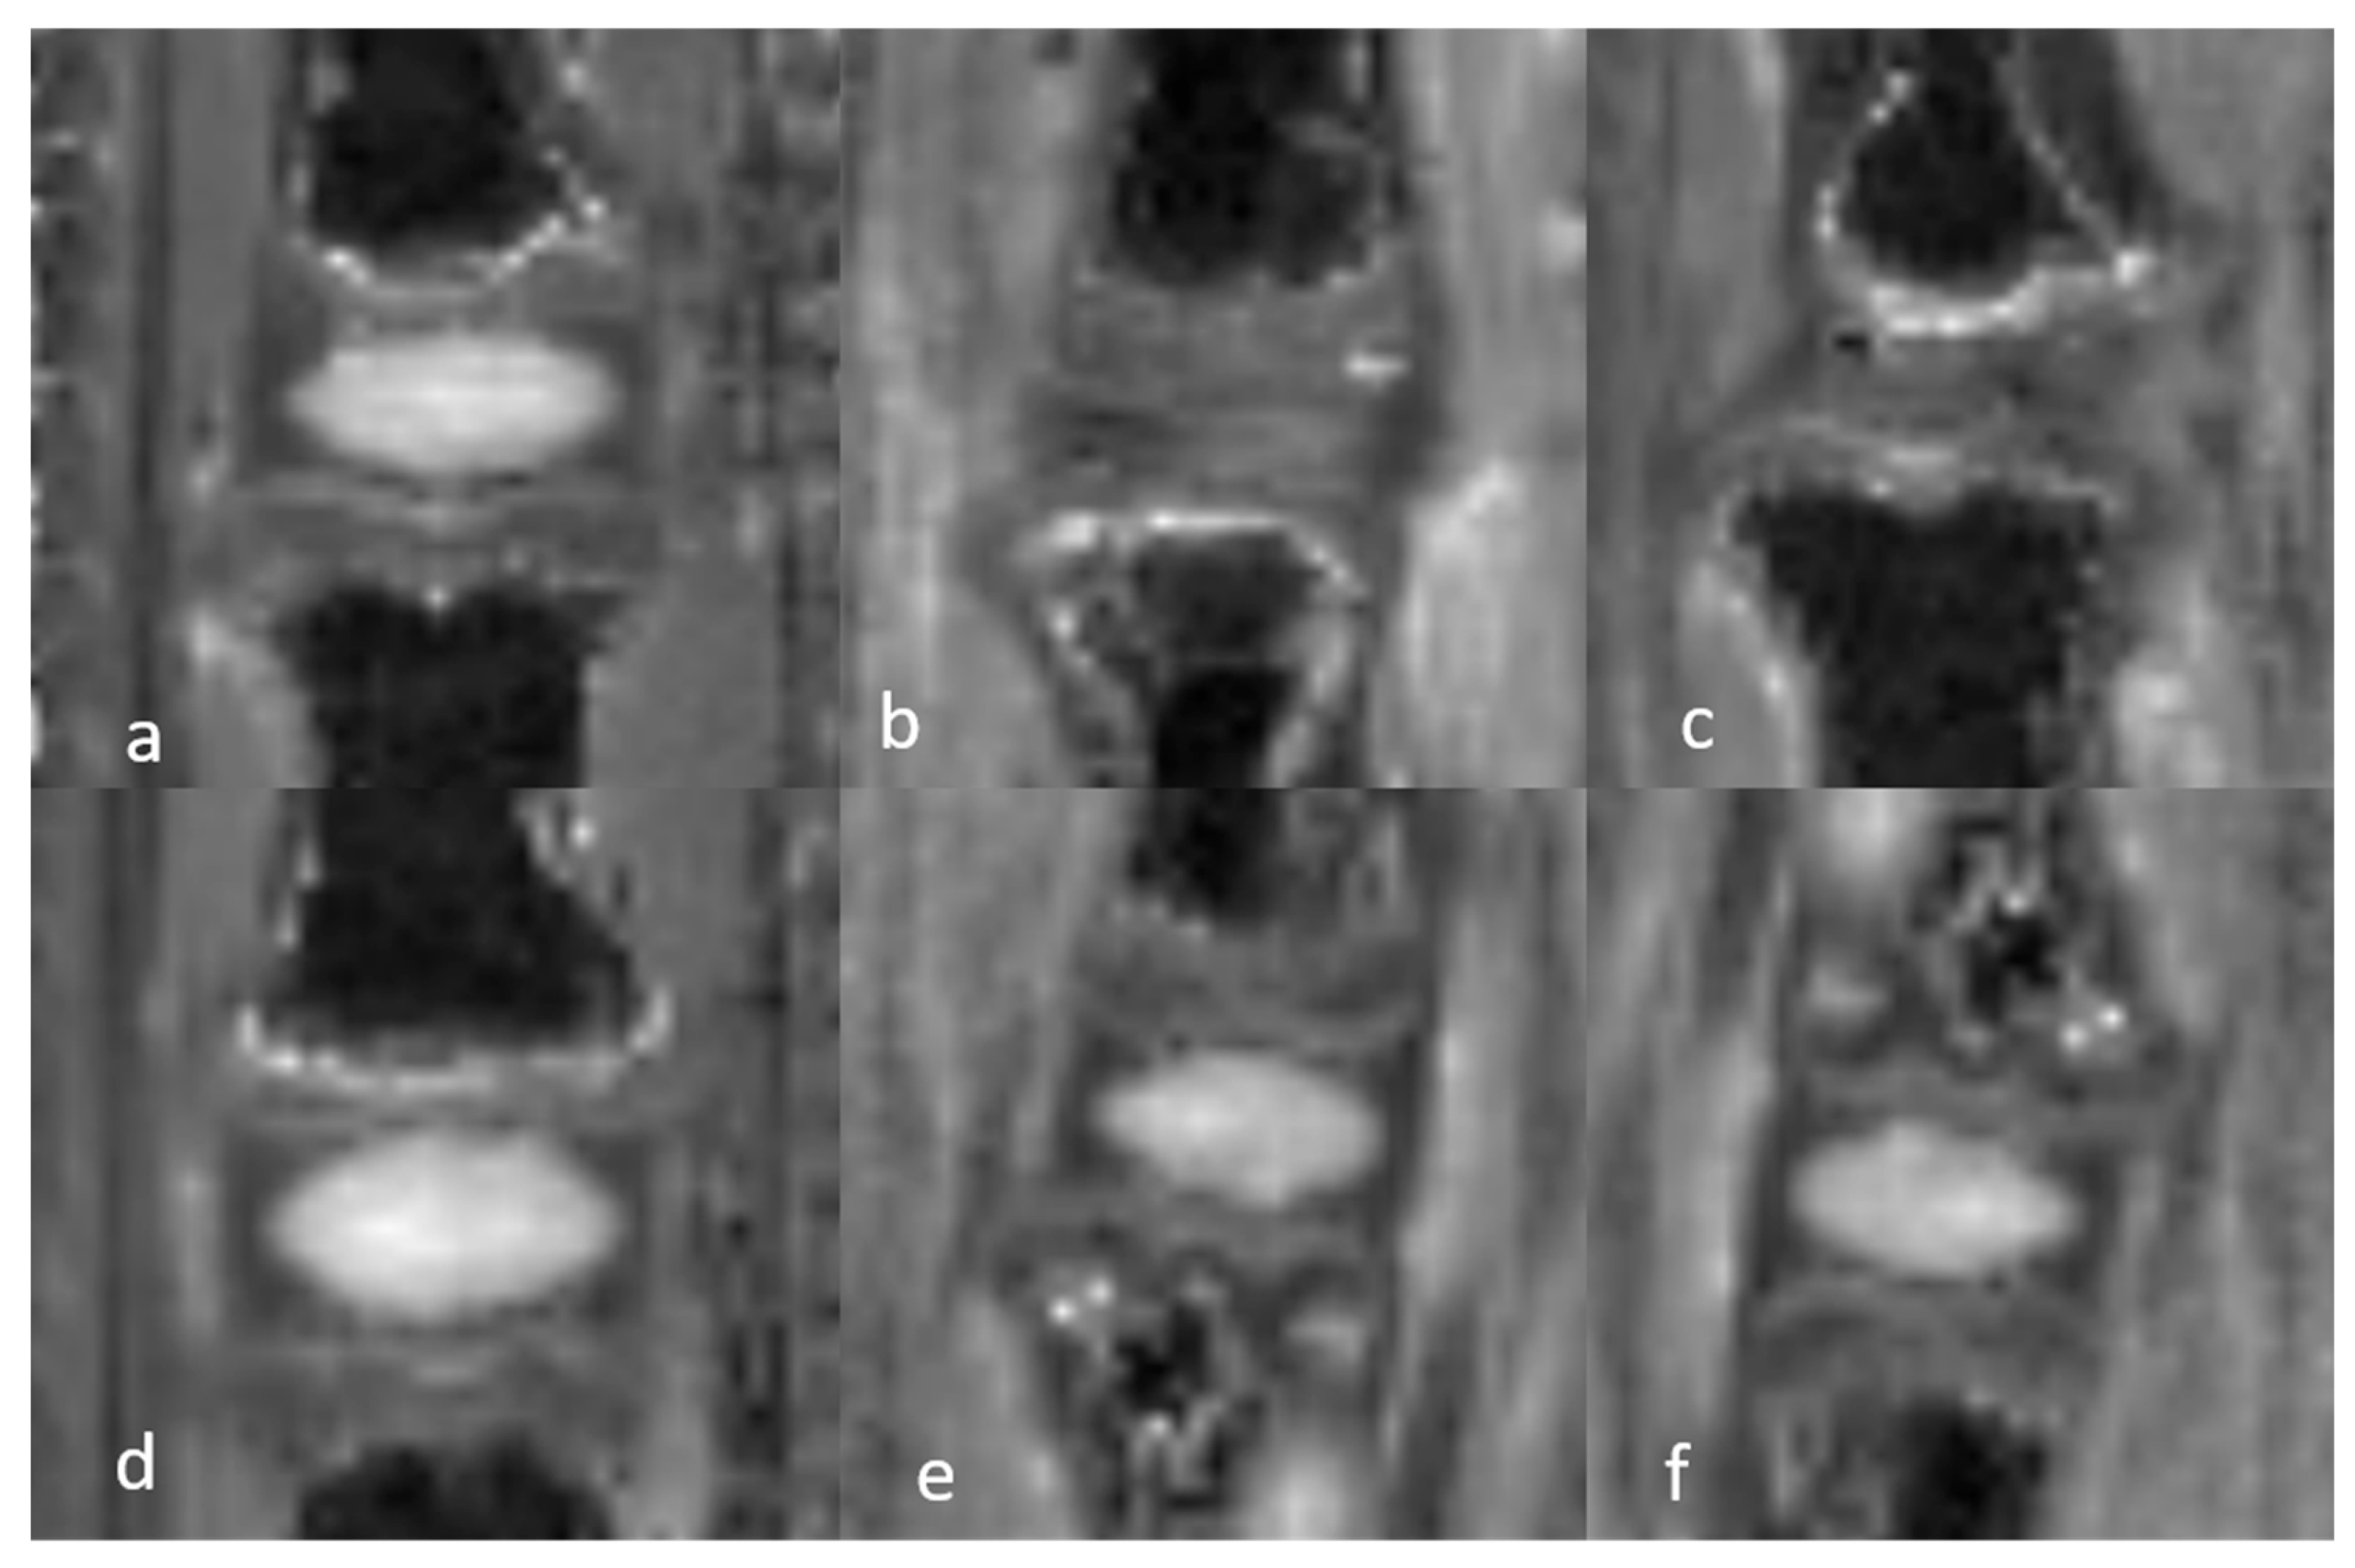

3.1.3. Quantitative Analysis of the Normal DVC (Table 4)

3.1.4. Quantitative Analysis of the DVC in DDD Rats (Table 4)

3.1.5. Semiquantitative and Quantitative Values of the Healthy DVC (Table 5)